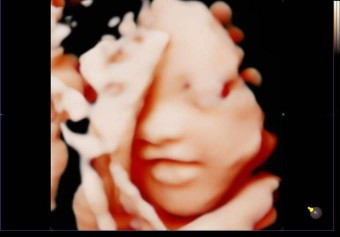

จ๊ะเอ๋ จมูก ปากของหนู มือของหนูปิดหน้าค่ะ